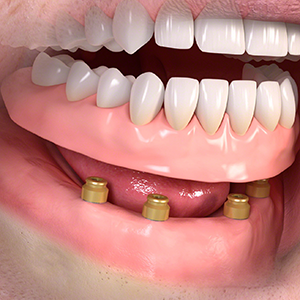

(インプラントに義歯を固定します)

・2~4本のインプラントによって入れ歯を固定します。

全ての歯を失った。

インプラントを埋める。 (​2~4本)

インプラントに凸型の装置を装着。

義歯に付けた凹型の装置と接続させる。 義歯を自分で取り外して洗浄します。